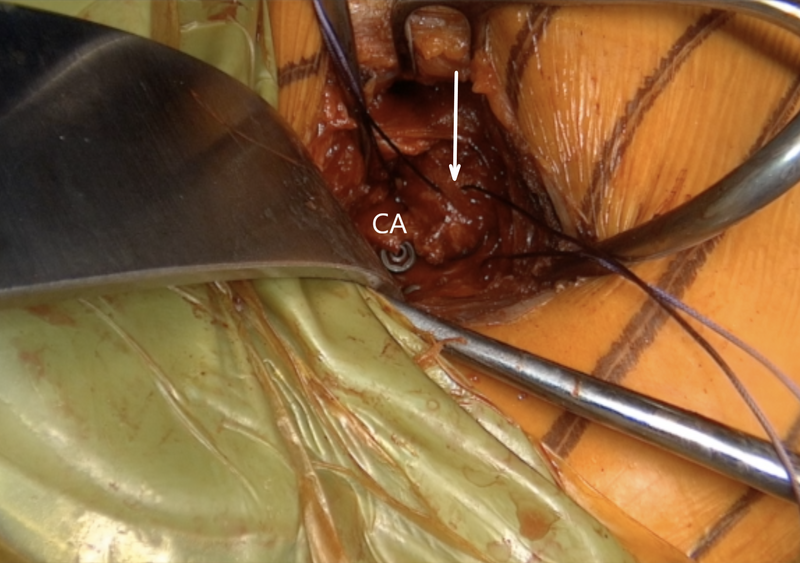

Left shoulder of a patient placed in a semi beach-chair position. Finally, the anterior capsule (white arrow) is reconstructed by the imbrication of the coracoacromial ligament (CA) with a resorbable suture. It is crucial that during the reconstruction, the arm is placed in adduction, anterior forward flexion, and external rotation. In this figure we see that the humeral head is stil anteriorly dislocated.